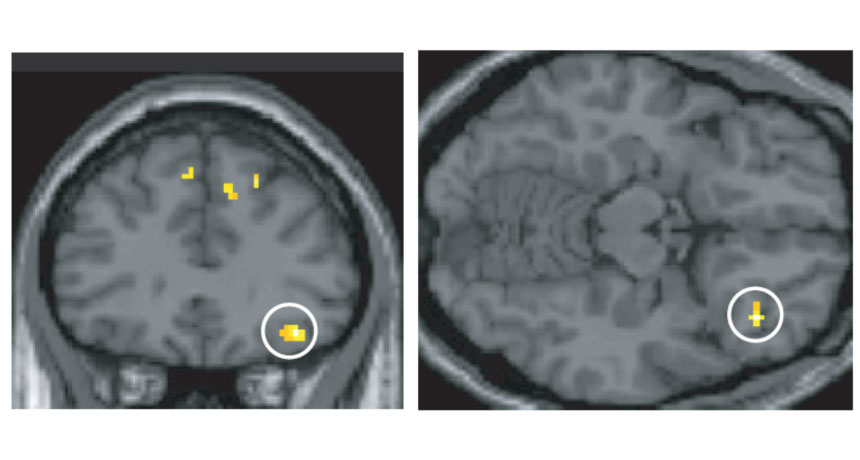

BRAIN BRIDGE  The right orbitofrontal cortex (circled in two different views of the brain) is one of two brain regions that serve as an interface between odor and language networks, new experiments show.